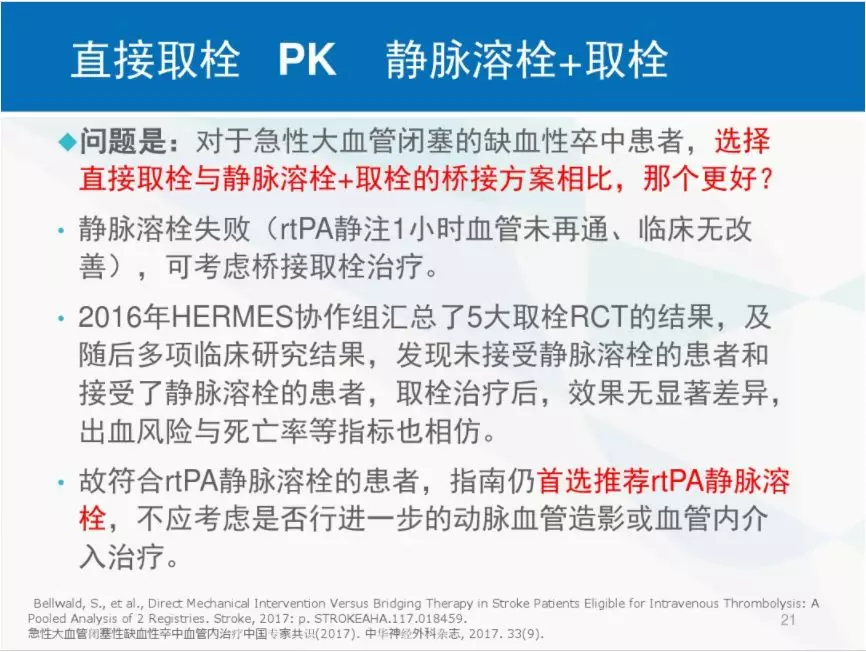

目前,对于静脉溶栓时间窗内的患者,静脉溶栓是首选的治疗方案,在早期关于取栓的5项阳性随机对照研究中,90%以上的患者均为静脉溶栓基础上进行机械取栓的桥接治疗。

多种研究结论

➣对于急性前循环大血管闭塞患者,直接取栓和桥接治疗似乎同样有效;

➣有必要进行RCT研究比较两者的有效性和安全性。

➣再通前采取静脉溶栓并不是良好预后的独立预测因素;

➣直接取栓能够获得与桥接治疗相同的再通率及良好预后,并不会提高介入相关并发症的发生。

➣对于大血管闭塞性缺血性卒中,介入治疗前的静脉溶栓并不能提供额外的获益;

➣需要大型RCT研究提供更可靠的证据。

➣直接取栓治疗具有与桥接治疗相同的疗效;

➣若经大型RCT试验证明后,对在院流程的改进发挥作用。

➣南京总医院领衔的联合国内21家卒中中心进行的急性前循环大动脉闭塞性卒中多中心注册(ACTUAL)研究,旨在比较适合静脉溶栓的患者4.5小时内直接机械取栓与桥接治疗的效果与安全性。

这项临床研究显示,对于适合静脉溶栓的患者,在4.5小时内跨过静脉溶栓而直接启动机械取栓可获得与桥接治疗类似的功能预后,不增加症状性颅内出血率及死亡率,并且无症状性颅内出血率更低。